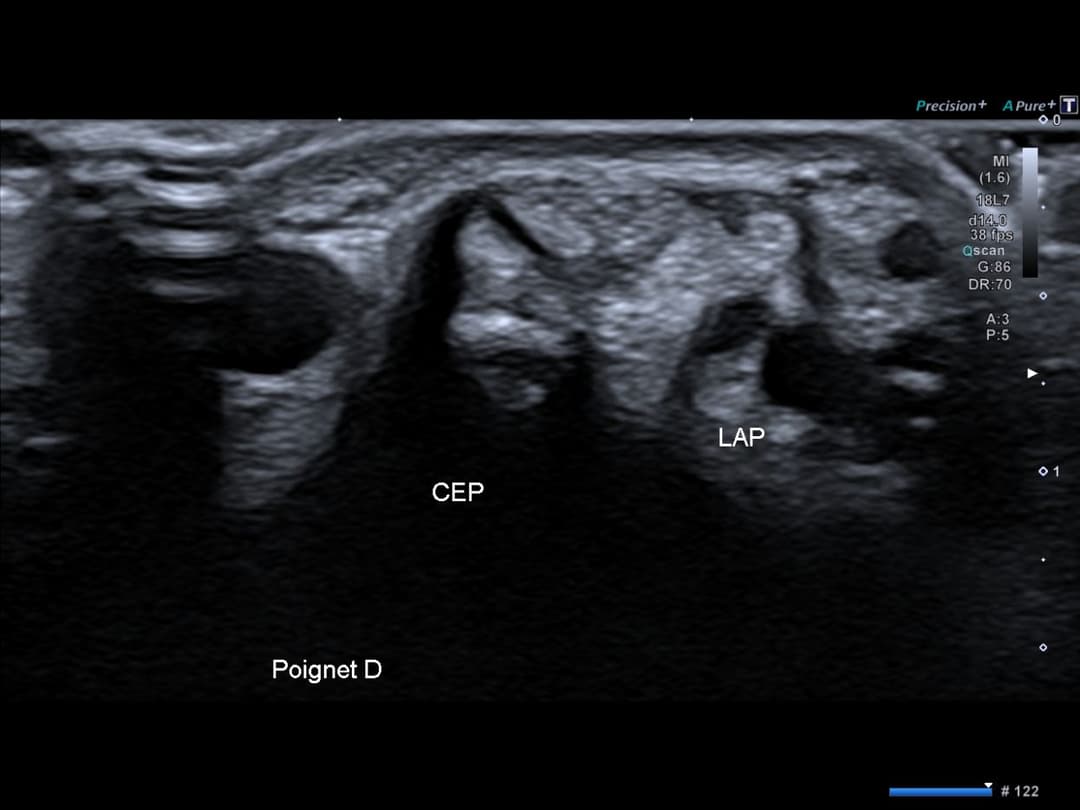

Intégrité des tendons de la 1ère loge tendineuse au niveau du poignet